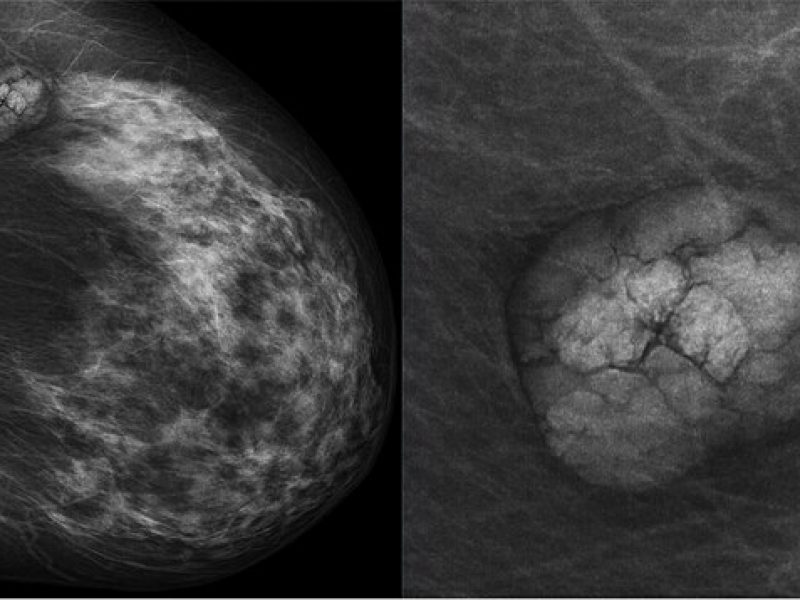

La mammographie, un examen essentiel pour le dépistage du cancer du sein, peut parfois engendrer une gêne ou une douleur. Cette douleur à la poitrine, bien que souvent temporaire, est une préoccupation courante pour de nombreuses patientes. La sensation de douleur lors de cet examen peut varier considérablement d’une personne à l’autre, et plusieurs facteurs peuvent en être la cause. Il est important de noter que, bien que la douleur de la mammographie puisse être inconfortable, elle est généralement de courte durée et diffère entre chaque patiente.

La douleur pendant la mammographie est surtout liée à la compression des seins. Le processus de compression est essentiel pour obtenir des images claires et détaillées, permettant ainsi une détection précise des anomalies. Cependant, cette compression peut exercer une pression sur les tissus mammaires, ce qui peut provoquer une sensation de douleur ou d’inconfort. L’intensité de cette douleur peut dépendre de la sensibilité individuelle de chaque patiente, de la densité du tissu mammaire et de la taille des seins (grosse ou petite poitrine).